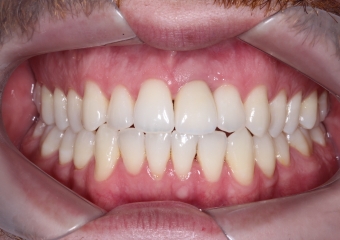

Foto Frontal Inicial 18-05-15